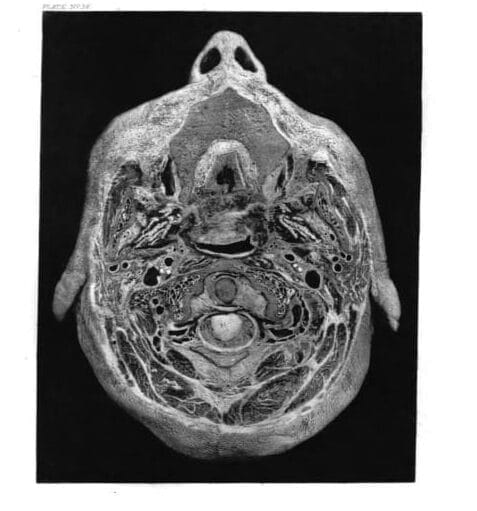

Sir William Macewen, pioneer of modern brain surgery, was born in western Scotland in 1848. In 1872 he graduated in medicine from the University of Glasgow, greatly influenced by Lord Lister. In 1875 he was appointed to the Glasgow Royal Infirmary, first as assistant surgeon, and in 1877 as full surgeon. Continuing his career as an educator and clinical surgeon, he became, in 1892, the Regius Professor of Surgery at the University of Glasgow. He continued to follow Lister’s antiseptic procedures and made significant advances in intracranial surgery, orthopedics, surgical removal of the lungs in the treatment of tuberculosis, endotracheal anesthesia, hernia surgery, and the surgical treatment of mastoid disease. He pioneered the use of photography for teaching medicine and surgery; and in his Atlas of head sections he published sections such as this one showing the spine, skull, portions of the brain, and even the ears and nose, rendering the body into abstract structures which can appear like works of art.